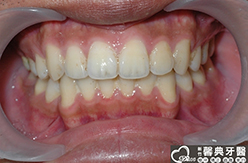

上、下顎前突,俗稱暴牙,由於上下前牙向前暴出,在外觀上容易產生牙齒外露的現象,雙唇較難自然閉合,嘴唇看也來也會比較厚。

患者︰趙同學,20多歲,學生。

主訴︰齒列不正,暴牙,不好看。

治療計劃︰上下顎齒列平整、後縮,重建正常咬合關係。